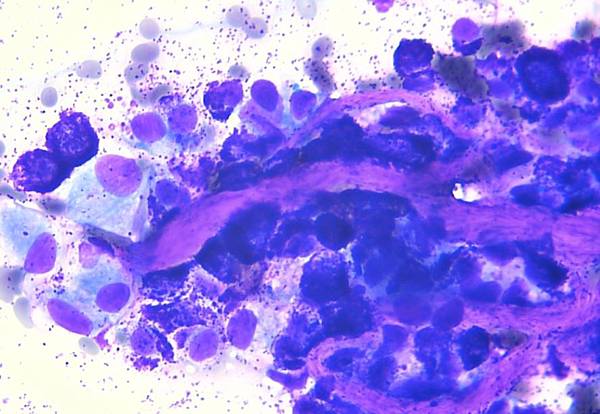

• 犬皮膚型肥大細胞瘤

肥大細胞瘤是犬皮膚最常見的腫瘤之一(約佔16~21%),平均發生年齡為9歲,好發品種包括:巴哥犬、拳師狗、牛頭梗、波士頓梗、拉不拉多、黃金獵犬、沙皮狗、雪納瑞及米格魯等。

肥大細胞瘤的臨床表現依腫瘤的侵犯性及惡性程度有很大的差異性,有可能為長期緩慢生長的單一小團塊(低惡性度),也可能為快速生長且極具侵犯性的高惡性度腫瘤,因此,當犬隻皮膚上發現任何不明團塊都不應該輕忽,應盡快就診進行採樣檢查。